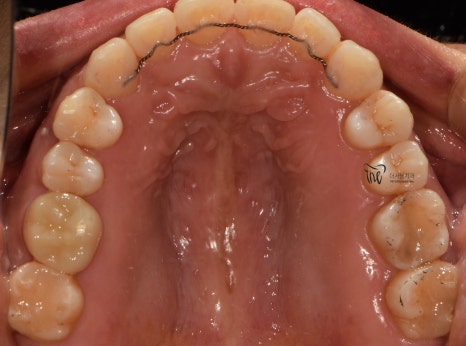

교합면에서 봤을 땐, 교정치료를 떠나서

선행해야 될 치료들이 많다는 것을 알 수 있습니다.

아말감이 수복 되어있던 곳의, 아말감 탈락에

따른 치질이 드러나 있다던지, 교합면의

다발성 우식증에 따라서 충치치료도 같이

병행을 해야 되는 상황입니다.

다만 하나 아쉬운 점은,

사랑니의 맹출 위치 불량에 따라서

바로 앞에 있는 제2 대구치는 발치 결정을

내리게 되었습니다.

이미, 치축이 상당히 쓰러져 있는 상황이며

업라이팅을 해드리기에는 시간이 오래 걸릴뿐더러

예후 또한 좋지 않을것으로 판단이 되어서

부정교합 2급 치료가 다 끝나는 시점에 맞춰서,

임플란트로 대체를 해드리기로 했죠.